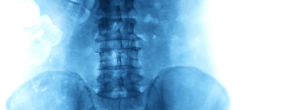

A dor crônica na Lombar é um problema que atinge milhares de pessoas no Brasil e que pode causar muita dificuldade no dia-a-dia delas. Viver com dores é sempre algo ruim e devemos procurar tratamento, mesmo quando elas são crônicas e nos acompanham há muito tempo.

Já falamos um pouco sobre as causas da dor crônica na lombar aqui no blog. Em resumo, ela pode ser causada por Lesões na coluna vertebral, Condições artríticas, como Artrose e artrite reumatoide, Problemas musculoesqueléticos, Stress ou ansiedade, Problemas de postura e estilo e vida.